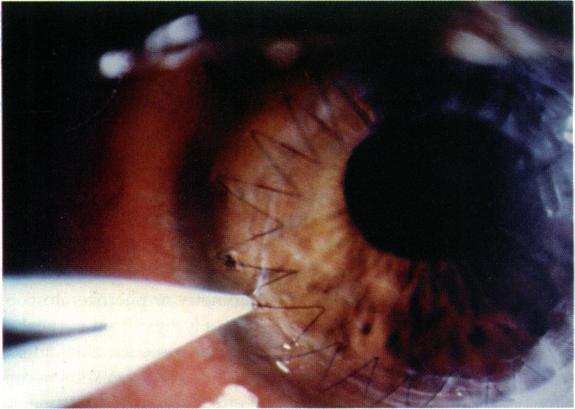

Post operative adjustment of a single continuous suture is an effective means of reducing post keratoplasty astigmatism. This study evaluates post keratoplasty keratometry following suture adjustment with an adjusted suture in place and after the suture is removed.

Average keratometric astigmatism was measured over 24 months time in 26 patients with an adjusted continuous suture and 24 patients with a continuous suture that was not adjusted. Average keratometry in 43 patients with an adjusted continuous suture was compared with 37 patients with combined continuous and interrupted sutures. Finally, suture out astigmatism in 19 adjusted patients was compared to six patients with no adjustment.

There was an increase in average corneal astigmatism over two years of 2.2 diopters in the adjusted group and 1.7 diopters in the non-adjusted group with sutures in place. One year following surgery, average keratometry flattened from 47.5 to 42.9 diopters in the adjusted continuous group and from 47.0 to 46.0 diopters in the group with combined continuous and interrupted sutures. Following suture removal, average astigmatism in patients who had suture adjustment was 4.4 diopters +/- 2.5 diopters (range 1-10 diopters), and 6.01 diopters (range 4-7) in the non-adjusted group.

Average post keratoplasty astigmatism increases after a continuous suture is adjusted but the increase is comparable to patients with acceptable astigmatism who do not require adjustment. More progressive corneal flattening over 12 months time is seen with a continuous suture than which combined sutures. Average suture out astigmatism was 4.0 diopters following suture adjustment, compared to an average of 8.4 diopters prior to adjustment.